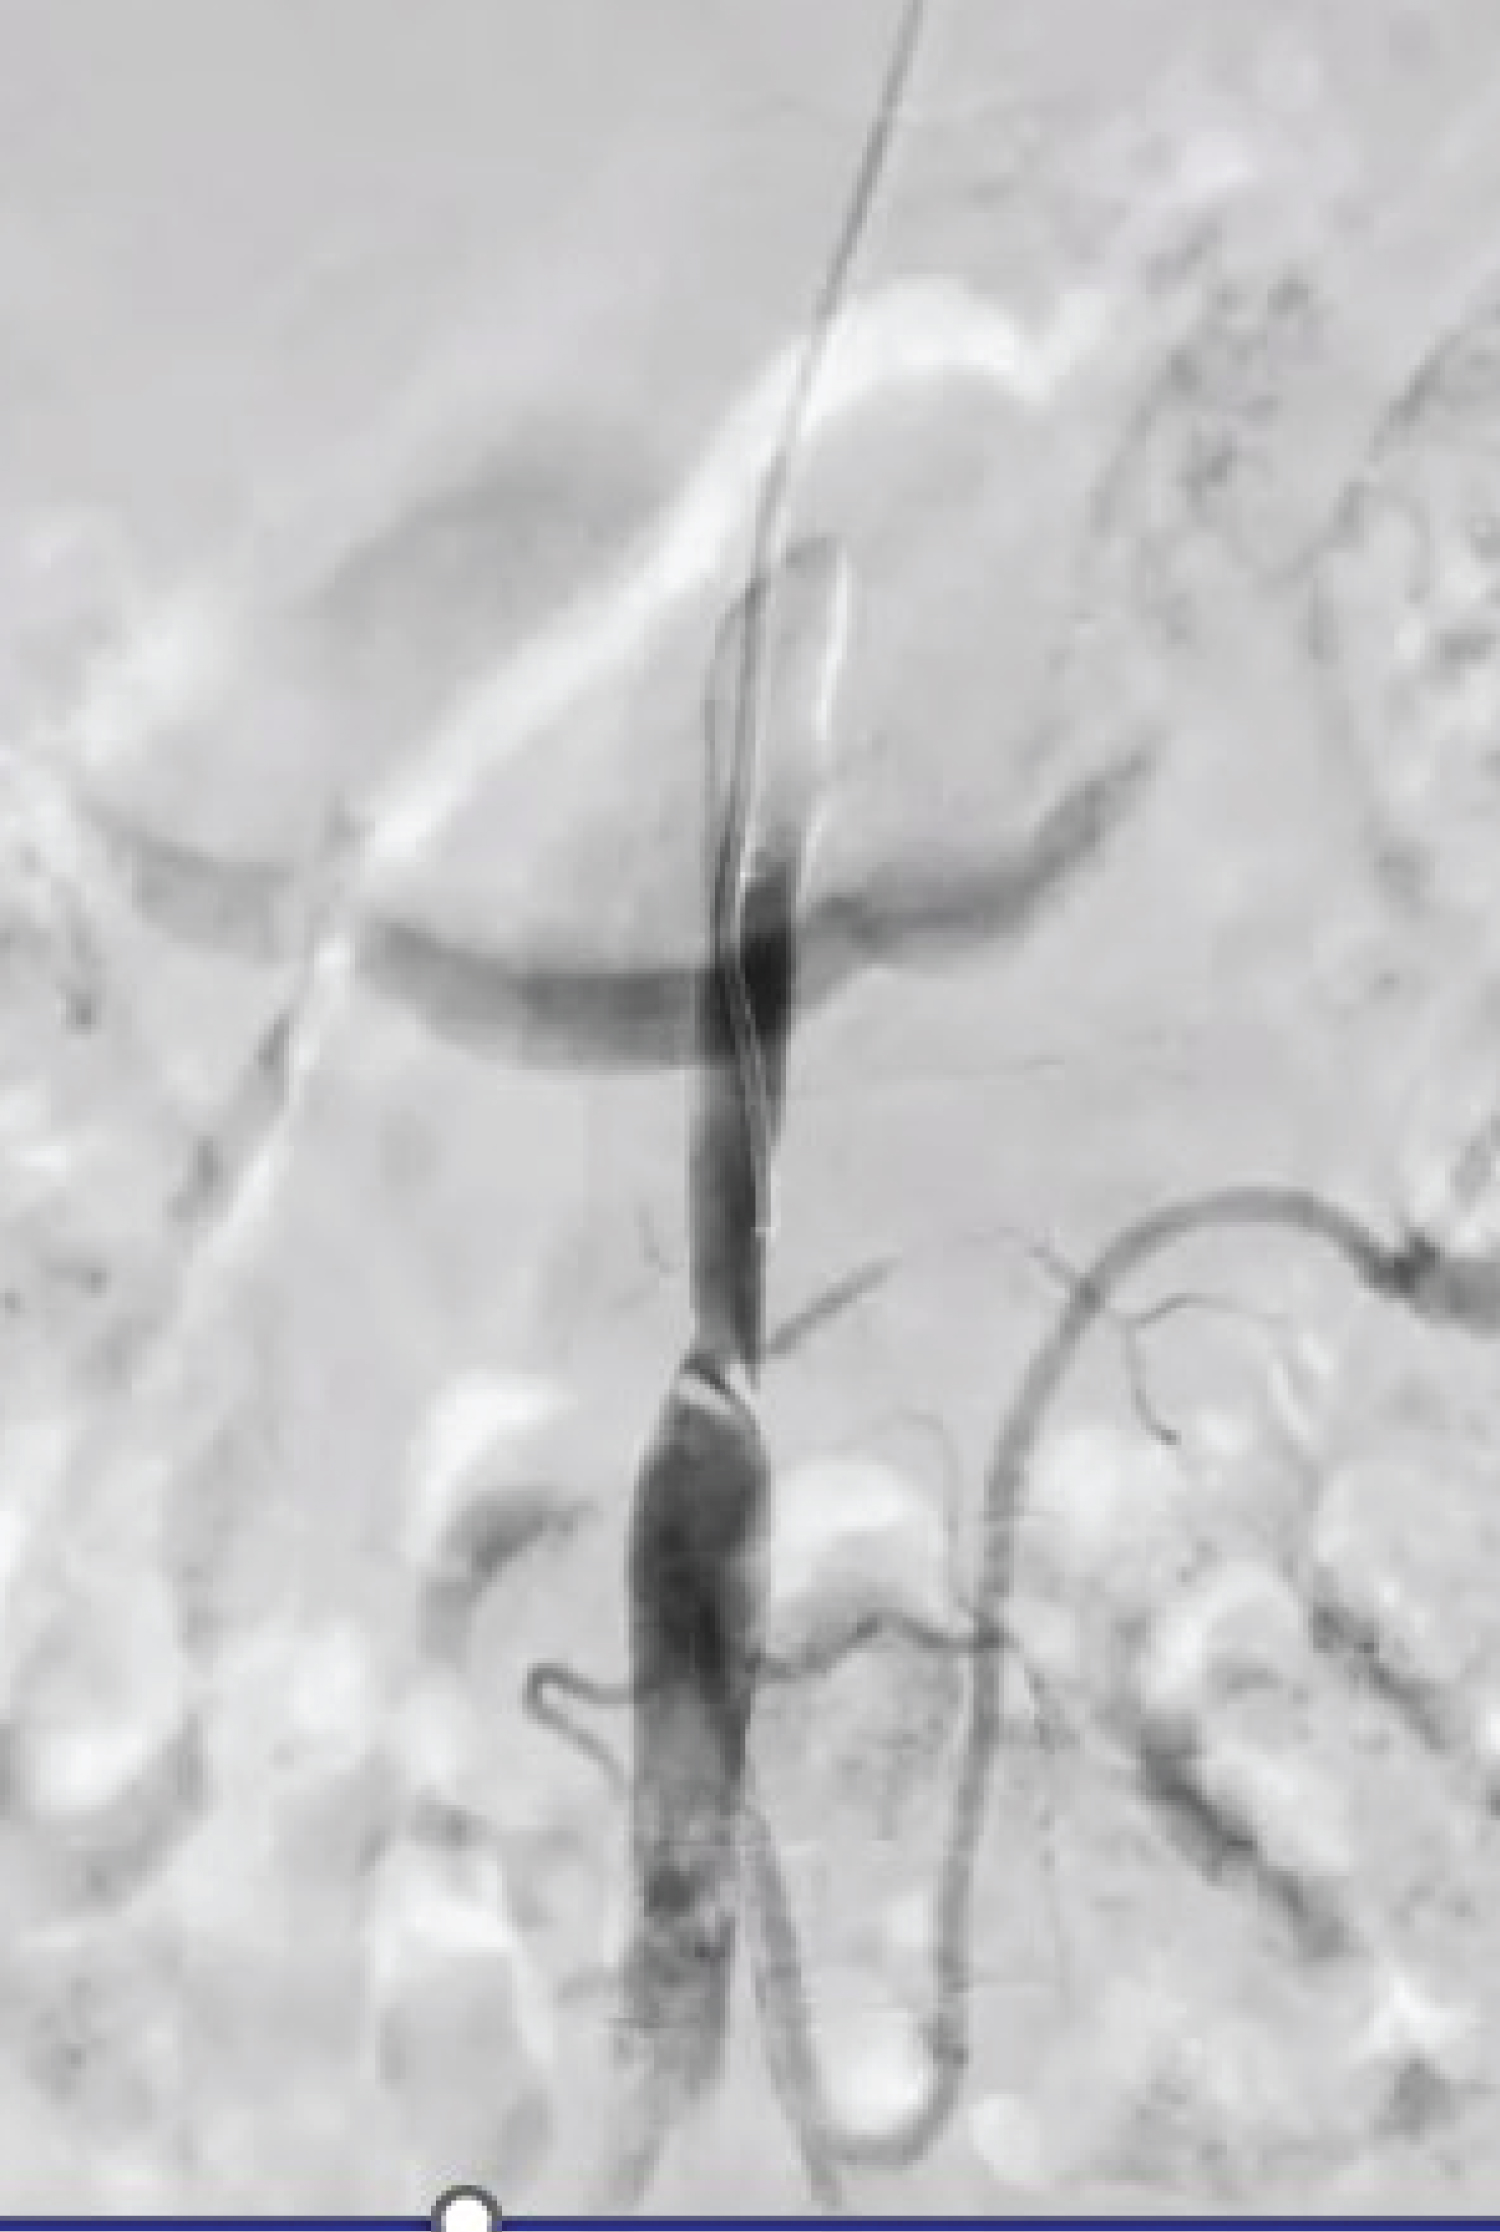

The procedure, performed under local anesthesia, involved a right femoral artery puncture. Heparin (100 IU/kg) was administered intravenously. A headhunter catheter was passed through the right femoral artery, revealing a distal flap in the infrarenal part, causing confusion regarding true or false lumen (Figure 2). To clarify, a left brachial artery access was taken, confirming the true lumen. The catheter was advanced, confirming total cutoff in the infra-renal aorta (Figure 3). Further, a terumo 0.035 wire was passed through the catheter and snared out through the right femoral artery access, and a multi-marker pigtail catheter was passed over it. A check shoot by pigtail shows similar findings as the CT aortogram. The lesion in the aorta was sequentially balloon-dilated with Cordis POWERFLEX PRO 12 mm × 6 cm balloon. Post-balloon dilatation check shoot shows improved distal flow. The suprarenal segment was stented with the Cordis SMART CONTROL NITINOL stent 14 mm × 60 mm, and the infrarenal segment was stented with the SMART CONTROL STENT 12 mm × 80 mm, with around 10 mm overlapping with the first stent (Figure 4-left image). The post-stent angiogram reveals good flow across the aorta with improved distal circulation with slow flow in right renal artery which we thought would improve by anticoagulation (Figure 4-right image). Five days after aortic angioplasty, the patient complained of persistent abdominal pain, and hypertension persisted. So, we decided to conduct a repeat CT Aortogram. The repeat CT Aortogram revealed a patent stent with good flow, and the celiac, SMA, IMA, bilateral common, external, and internal iliac were normal. There was a critical stenosis (> 80% ostial stenosis) in the left renal artery and right renal artery total cut off from ostium (Figure 5). Consequently, we proceeded with PTRA. A check shoot with a sim catheter showed similar finding as of CT Aortogram. A 0.014 wire was crossed, and the right renal artery ostium was dilated using a 4.5 × 20 mm PIPIT balloon. The right renal artery was stented with a RENOFIT 5 × 15 mm stent. The left renal artery was stented with a RENOFIT 6 × 15 mm stent. Post-angioplasty revealed bilateral good-caliber renal arteries with good flow (Figure 6). Thirty minutes after the procedure, the patient developed right hemiparesis. On examination, the patient was conscious, oriented, with power of 2/5 in both upper limbs and lower limbs. NCCT showed left ganglio-capsular intraparenchymal bleed, which was managed conservatively. Post-renal stenting, the patient's abdominal pain diminished and blood pressure significantly came down. After 10 days, the patient was discharged with power of 4/5 in both upper and lower limbs in an ambulatory condition. Hypertension was well controlled with only amlodipine 5 mg. The patient has been doing well for the last 11 months with a single antiplatelet agent.

Figure 2: Headhunter catheter passed through the right femoral artery access, revealing a distal flap in the infrarenal part, causing confusion regarding true or false lumen. View Figure 2